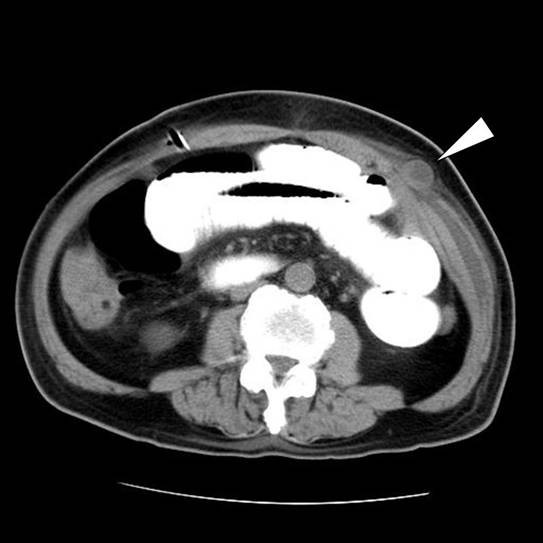

From jmedicalcasereports.biomedcentral.com

Port site herniation of the small bowel following laparoscopyassisted Pinhole Fistula A cause of persistent incontinence from a kock pouch. a rectovaginal fistula is an epithelialized communication between the rectum and the vagina (when distal to the dentate line, it. Vvf is an abnormal fistulous tract. Anatomy of the perineal body, distal vagina, rectum, and anus. (3.1) small and pinhole fistulas. what is a vaginal fistula? vesicovaginal. Pinhole Fistula.